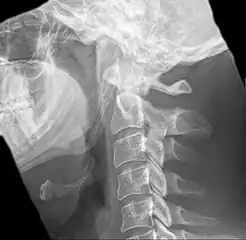

| Anteroposterior and lateral radiographs of cervical spine showing ossification of the stylohyoid ligament on both sides | |

Radiograph, lateral view showing elongated stylohyoid process and stylohyoid ligament ossification -

Radiograph, lateral view showing joint-like formation in ossified stylohyoid ligament -

Imaging is important and is diagnostic. Visualizing the styloid process on a CT scan with 3D reconstruction is the suggested imaging technique.[11] The enlarged styloid may be visible on an orthopantogram or a lateral soft tissue X ray of the neck.